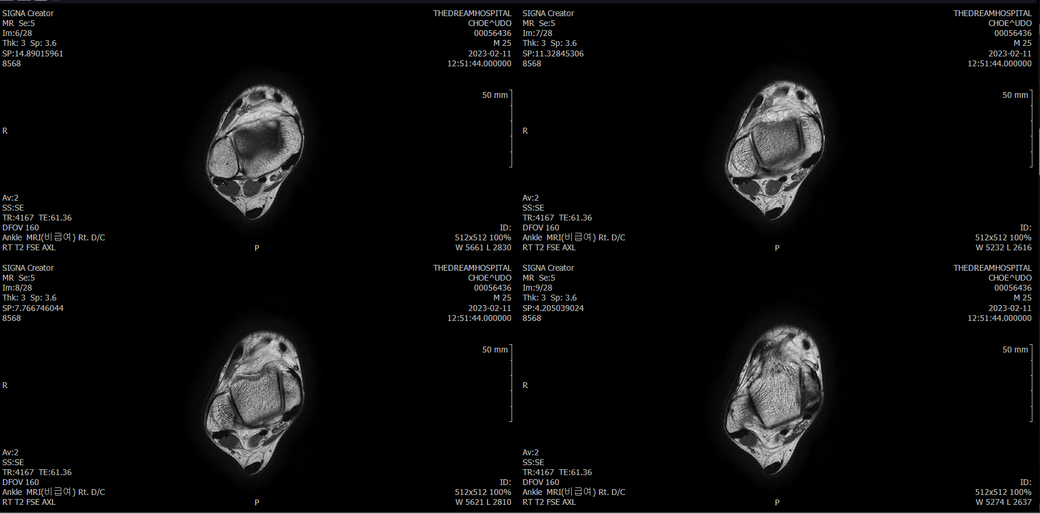

오른발목 mri 전체사진입니다. 제가 병원을 갈수없는상황인지라.... 봐주시면 감사하겠습니다.

엑스레이에서는 문제가 없다고 하여 오른발목 mri촬영했습니다.

우선 전반적으로 봤을 때 큰 이상은 없어보입니다.

전거비인대 등도 저명한 손상은 없는 것 같아 보이지만, 어느 부분의 통증 등으로 인해 촬영을 하셨는지 말씀을 해주신다면 보다 정확한 병변파악이 가능하겠으며, 병원에서 판독이 완료되신다면 전화 등으로 문의를 해보시는 것이 좋겠습니다.